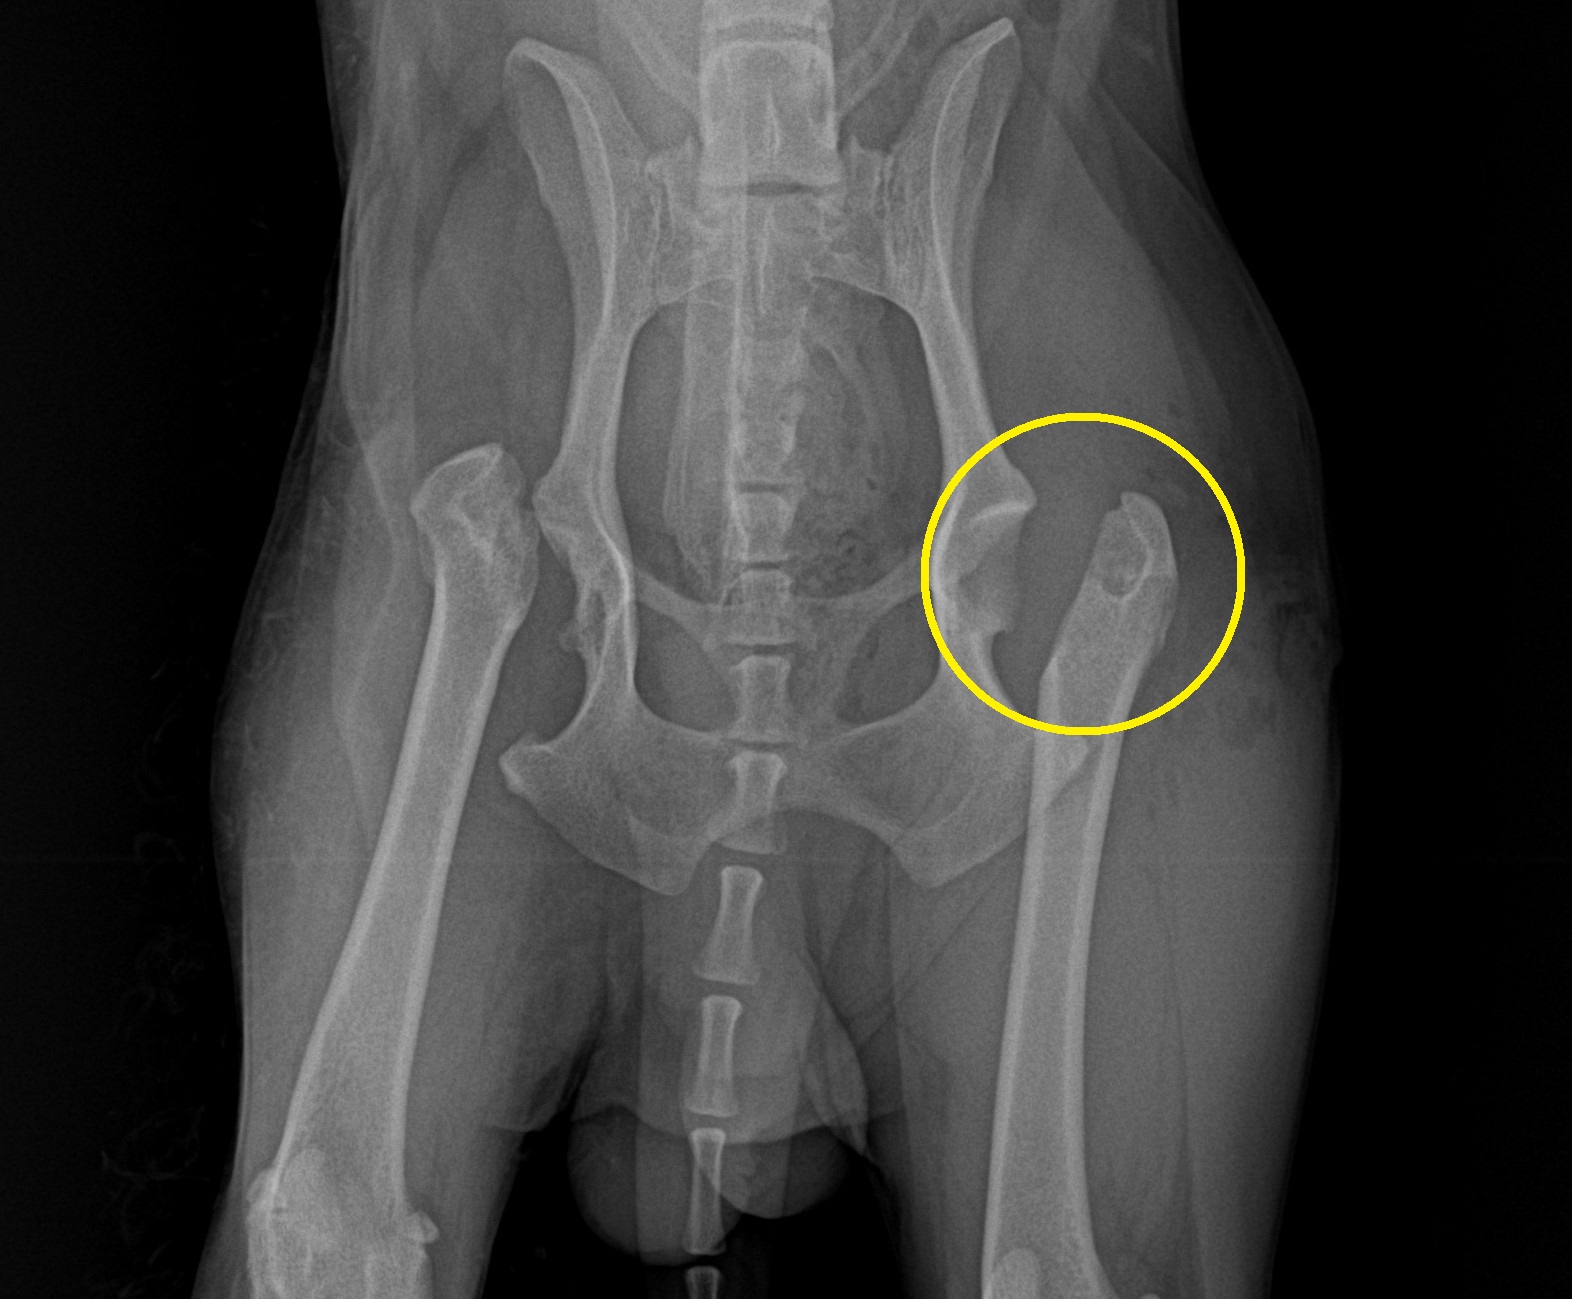

手術では、左大腿骨頭を切除し、術後のレントゲンでしっかりと確認(黄丸)できました。